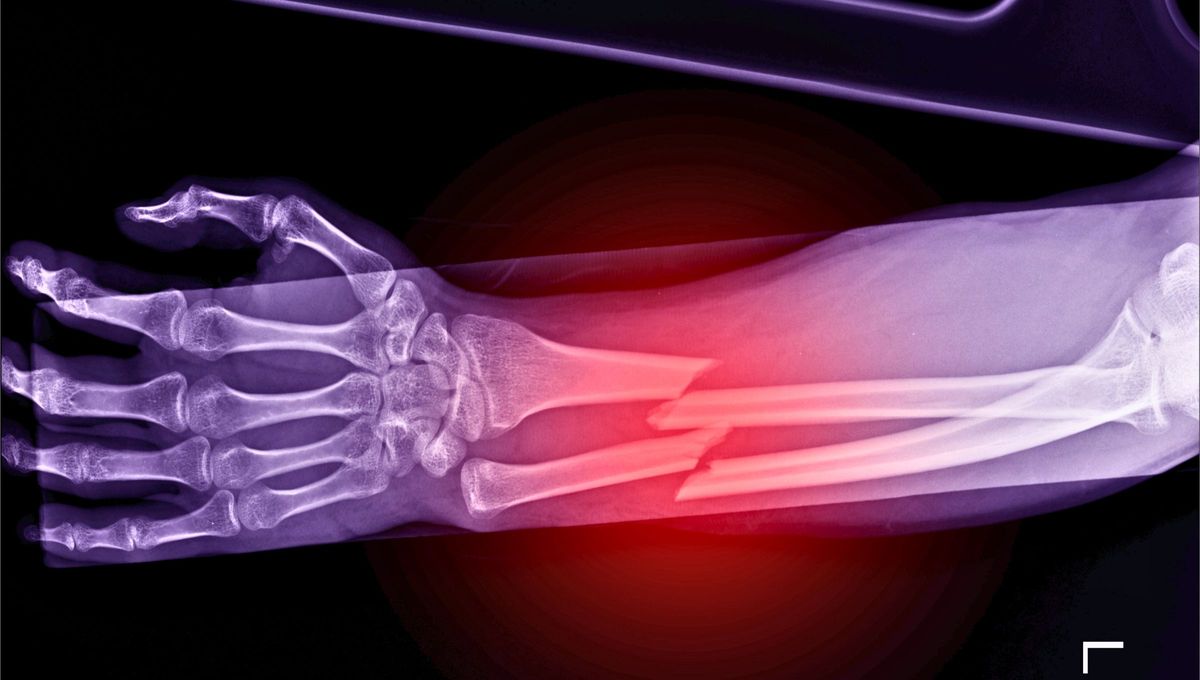

Por qué algunas personas nunca se quiebran un hueso

Profesionales de la salud expertos en kinesiología indagaron sobre una cuestión que, hasta el día de hoy, no tenía explicación: ¿Existen personas que son más propensas a sufrir quebraduras en sus huesos y otras que no? Te lo revelamos.